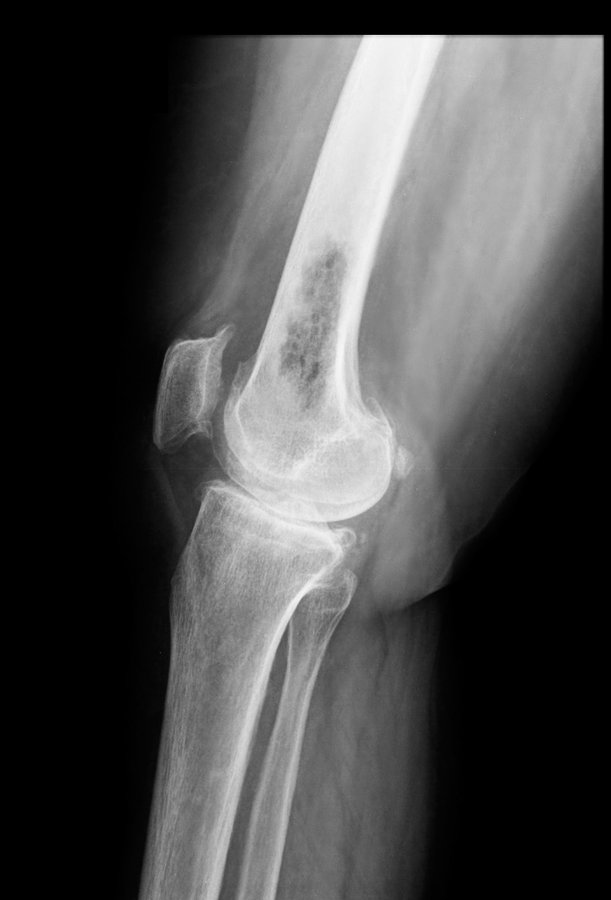

La biopsia de los huesos sirve para confirmar el diagnóstico de un trastorno, para estudiar una anormalidad o distinguir un tumor. Una aguja se inserta por la piel y dentro del hueso para extraer una muestra. Aquí lo que debes saber ow.ly/MFe850zEbzK Vía